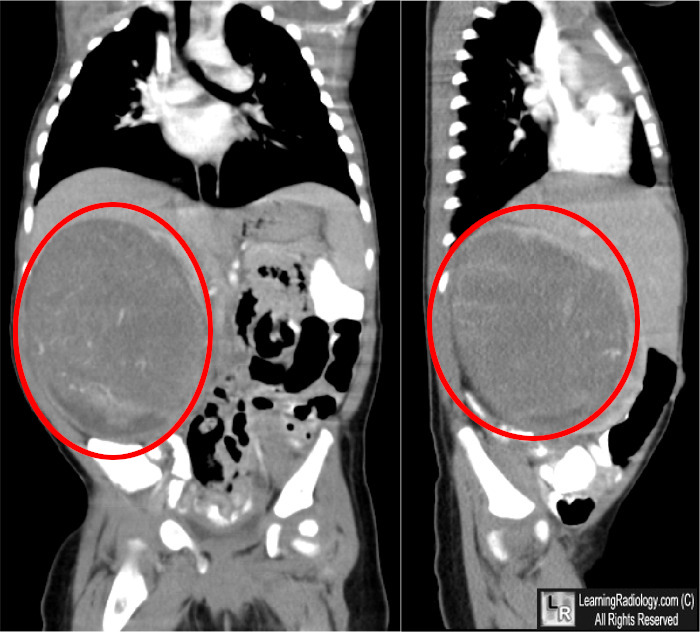

Nefroblastoma

- Descrizione: Il nefroblastoma, o Tumore di Wilms, è un Tumore Maligno che deriva dal primitivo abbozzo renale. Rappresenta la neoplasia renale primitiva più frequente in età infantile.